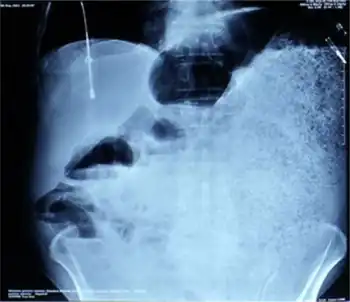

| Toxic megacolon associated with ulcerative colitis. | |

Toxic megacolon

Toxic megacolon is mainly seen in ulcerative colitis and pseudomembranous colitis, two chronic inflammations of the colon (and occasionally, in the other type of inflammatory bowel disease, Crohn's disease). Its mechanism is incompletely understood. It is probably due to excessive production of nitric oxide, at least in ulcerative colitis. The prevalence is about the same for both sexes.